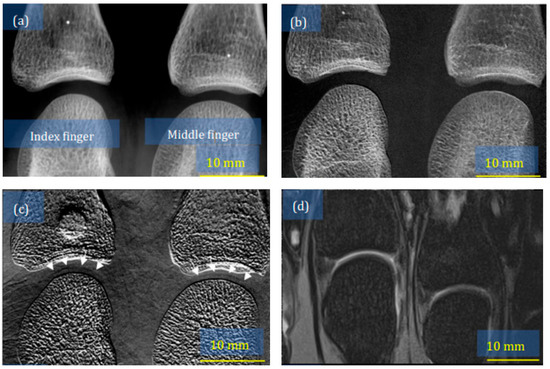

- Yoshioka, H.; Kadono, Y.; Kim, Y.T.; Oda, H.; Maruyama, T.; Akiyama, Y.; Mimura, T.; Tanaka, J.; Niitsu, M.; Hoshino, Y.; et al. Imaging evaluation of the cartilage in rheumatoid arthritis patients with an x-ray phase imaging apparatus based on Talbot-Lau interferometry. Sci. Rep. 2020, 10, 6561. [Google Scholar] [CrossRef]